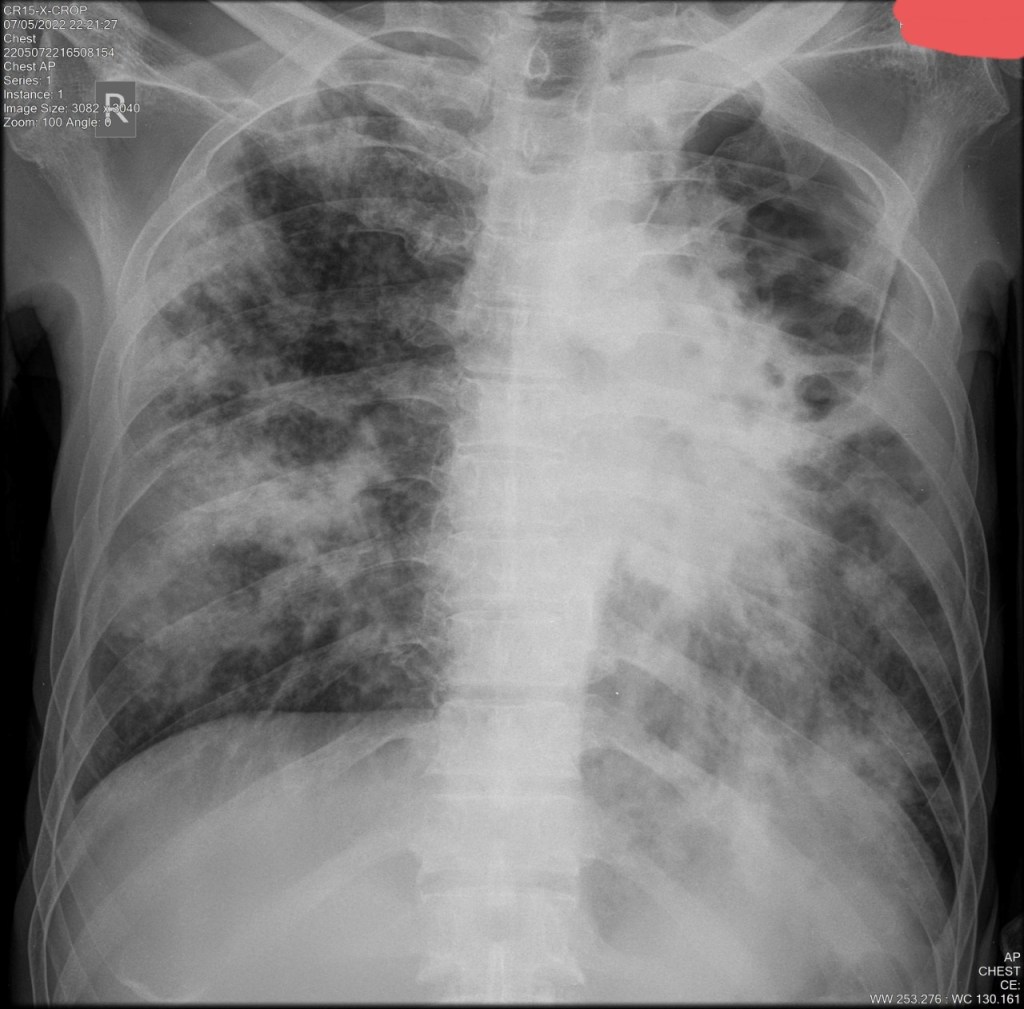

c. Nodul-Massa

– Nodul < 3cm : granuloma, Ca Paru, metastasis, hemartoma

-Massa> 3 cm : Ca Paru, granuloma, hamartoma

– Massa multiple: infeksi. metastasis, sarkoidosis, wegner